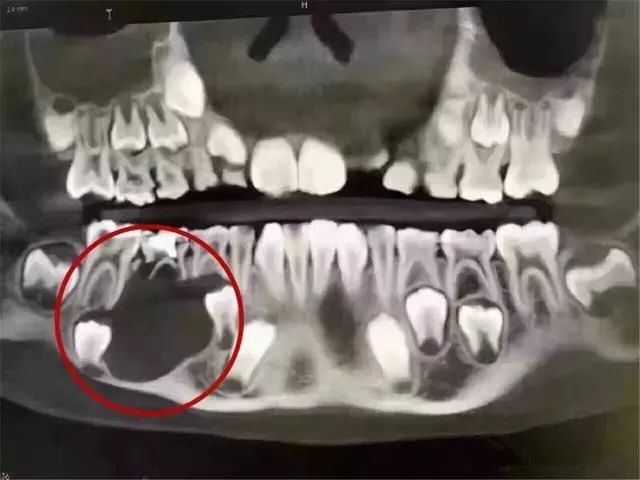

我哋再睇另一個9歲孩童的案例

一個9歲的孩子,因為家長冇重視乳牙護理同齲齒治療,嗰顆乳牙底下嘅頜骨大面積吸收!哎,囊腫導致嘅乳牙根尖周炎,都可能係頜骨吸收嘅其中一個原因(因為冇詳細資料同醫生嘅診斷)。

圖上面嘅黑影係頜骨破壞嘅部分圖像,太驚慄喇